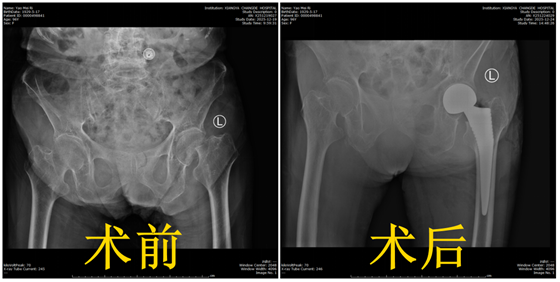

近日,湘雅医院骨科常德病区联合多学科团队,成功为一名97岁高龄、合并多种严重基础疾病的股骨颈骨折患者实施“人工髋关节置换术”。术后患者恢复良好,目前已顺利出院。该例极高龄、高风险患者的成功救治,充分彰显了医院在高龄骨科手术领域的精湛技术、高效的多学科协作能力以及贯穿始终的以患者为中心的人文关怀。

患者因不慎摔倒导致股骨颈骨折。对于超高龄老人,此类骨折常被称为“人生最后一次骨折”,致死致残风险极高。更为棘手的是,患者长期患有高血压、冠心病、重度骨质疏松等多种基础疾病,身体耐受性较差。手术面临心、肺、脑等多系统风险;但若采取保守治疗,长期卧床又极易引发致命并发症。经与家属深入沟通,医疗团队确立了清晰目标:通过周密评估与微创手术,帮助患者争取重新站立的机会,最大限度提升其生存质量。

手术当日,在多学科团队的全程保障下,关节外科周天宝主任医师带领手术团队精准施术、紧密配合。凭借丰富的高龄手术经验,仅用时40分钟便顺利完成人工股骨头置换术。术中出血少、创伤小,麻醉团队全程严密监测生命体征,确保血压、心率等指标平稳,整个手术过程顺利平稳。